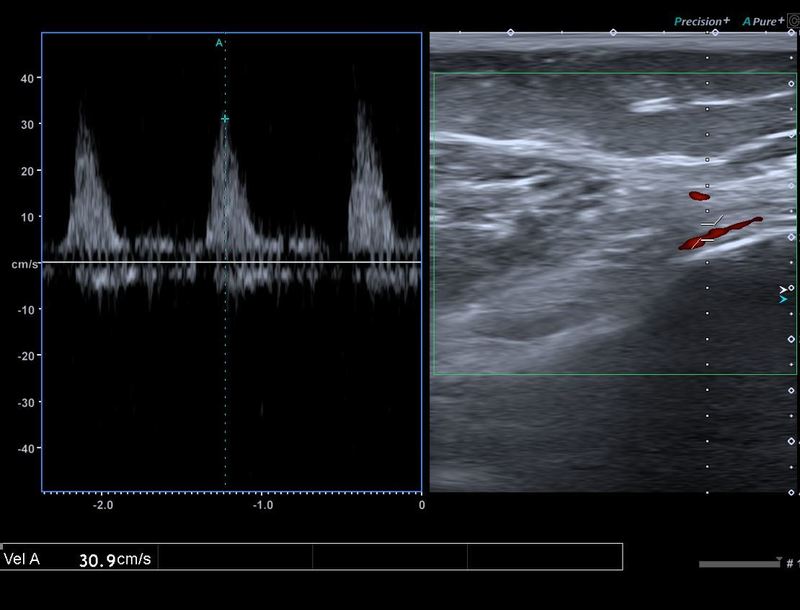

超音波検査

→膝関節の炎症が起こっていることが明確になった 水腫

水腫 血流計測 25mm/sec以上が異常